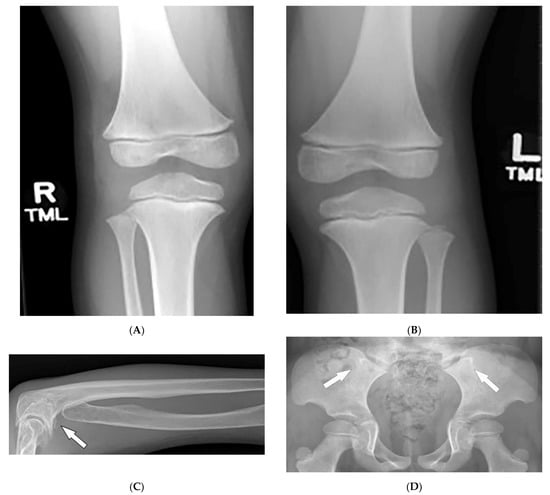

3.9. Fong Disease

| Fong (Nail–patella) syndrome | Hypoplastic nails, triangular lunulae Hypoplastic patellae Focal segmental glomerulosclerosisLester iris | Bilateral absence of patellae Posterior iliac horns (Fong’s prongs) Subluxation of radial heads |